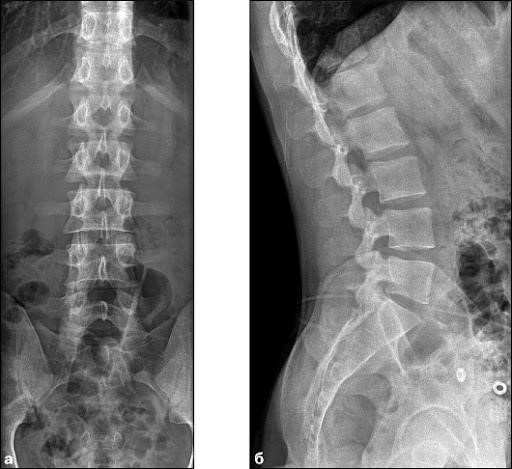

В диагностике заболеваний позвоночника ключевую роль играют рентгенологические методы.

- Рентгенография позвоночника проводится в двух проекциях: фронтальной и боковой. Для более детального изучения межпозвонковых суставов и отверстий используются косые проекции. Также возможно применение рентгенографии при максимальном сгибании и разгибании позвоночного столба. Рентгенография шейного отдела позвоночника позволяет получить информацию о телах позвонков, межпозвонковых дисках, суставах и остистых отростках. Врач анализирует форму, расположение и структуру костных элементов. Это исследование помогает выявить дегенеративные изменения, травмы и аномалии развития. При максимальных сгибаниях и разгибаниях можно обнаружить смещение структур относительно друг друга. Рентгенография грудного отдела позвоночника также позволяет оценить тела позвонков, межпозвонковые диски, поперечные и остистые отростки. Можно различить структуру реберно-позвоночных суставов и просмотреть позвоночный канал на протяжении всего отдела. Это исследование помогает диагностировать воспалительные процессы, дегенеративно-дистрофические изменения, аномалии развития и травмы. Рентгенография пояснично-крестцового отдела позволяет изучить форму, контуры и структуру позвонков, а также оценить статическое состояние позвоночного столба. Также исследуются суставные поверхности подвздошной кости и крестца. При проведении функциональных проб можно выявить как патологическую подвижность, так и её утрату.